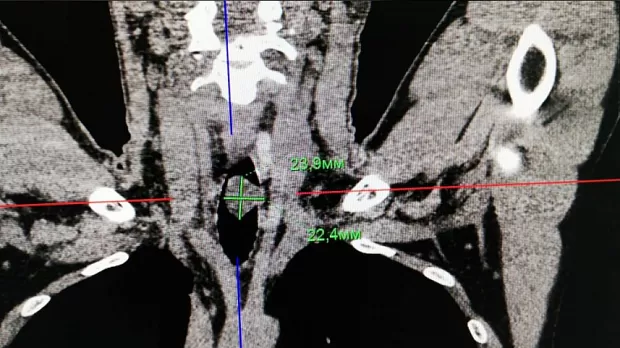

Пациент Р. 1988 г.р., госпитализирован в клинику для дообследования и оперативного лечения с диагнозом: образование в/3 трахеи. На амбулаторном этапе при бронхоскопии выявлено образование в/3 трахеи, биопсия не взята. После госпитализации в нашу клинику проведено КТ, на томографии имеется образование размерами 2.4х2.3 см, с ножкой 13 мм, с плотностью до 40 ед, имеется инвазия в области ножки в подслизистый слой на 6 мм, рядом увеличенный лимфоузел.